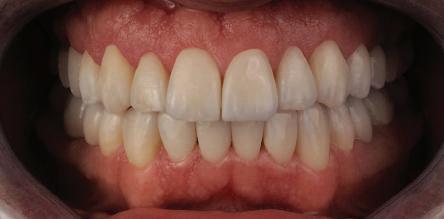

След стабилизира не на ставите и долната челюст в те рапевтична позиция постигнах орто донтски премествания и скелетни ко рекции, които обикновено са възмож ни единствено посредством ортогнат на хирургия. Преминах от аналогов мо дел на работа към изцяло дигитален, за да се хармонизира лицевата естетика чрез Digital Smile Design, като същевре менно обаче изработих функционален аналогов восъчен моделаж и на двете че люсти, за да мога да приложа оклузална та концепция на Славичек. След което напаснах препарациите с аналоговия во съчен моделаж при изцяло дигитални ус ловия с цел фрезоване на короните. Всич ки тези комбинации правят случая из ключително комплексен. В крайна сметка този сложен случай бе лекуван с най-добрата възможна ком бинация от възможности, които ана логовият и дигиталният свят предла гат, за да се постигне красота, която е следствие от отлична функция. ОКЛУЗАЛЕН „БАЛЕТ“ С РОЗОВАТА ЕСТЕТИКА Клиничен случай, победител в категория „Комплексно естетично възстановяване“ в конкурса „Усмивка на годината 2022“ Преди След

7Dental Tribune Bulgarian Edition / октомври 2022 г. Преди лечението Фиг. 1 Фиг. 4 Фиг. 7 Фиг. 10 Фиг. 13 Фиг. 16 Фиг. 17 Фиг. 18 Фиг. 19 Фиг. 20 Фиг. 11 Фиг. 14 Фиг. 12 Фиг. 15 Фиг. 8 Фиг. 9 Фиг. 5 Фиг. 6 Фиг. 2 Фиг. 3

9Dental Tribune Bulgarian Edition / октомври 2022 г. След лечението За авторите: Д-р Манол Ивчев е създател на COLDY DENT Functional Atelier, завършва дентална медицина във ФДМ, София. Шест години е стажант в ортодонтска практика. Интересите му са изцяло насочени към функционалната дентална медицина. Посещава курсовете на Доусън и Льо Гал. Преминава редица обучения, акредитирани от Института на Славичек във Виена – VieSID. Впоследствие става най-младият инструктор във VieSID. Придобива права да преподава философията на проф. Рудолф Славичек в България. В практиката си се придържа към протоколите на Славичек за функционално лече ние и диагностика, тъй като те са насочени към комплексно лечение. Завършва всички нива за морфология на зъбите и моделаж при Janos Mako. Повишава знанията си по функционална ортодонтия чрез индивидуален курс в Румъния. Д-р Ивчев е и сертифициран зъболекар по лингвална ортодонтия от Катедрата по ортодонтия от Университета по стоматология в Тегу, Южна Корея. Сертифициран е и за лечение на ортодонтски аномалии чрез миофункционални апарати, а също и за ортодонтия, подпомагана от миниимпланти, отново от Университета по стоматология в Южна Корея. Завършва индивидуално обучение по функционална ортодонтия в Университета по дентална медицина в Богота, Колумбия, както и индивидуално обучение по функционална ортодонтия и физиотерапия по про токола на Mariano Rocabado. Има завършено индивидуално обучение по функционална зъботехника и функционален Wax-Up клас I,II и III. Завършва курс за Digital Smile Design и Skin Concept в Люксембург при Christian Coachman, Florin Cofar, Paulo Kano, Josef Kunkela, Livio Yoshinagа. Зт. Leandro Gambogi, Бразилия, завършва зъботехника през 1999 г. Експерт и пионер в дигиталната диагностика. Лектор и инструктор на курсове в областта на дигиталното протезиране. Понастоящем е главен изпълнителен директор и зъботехник в DENTALE DIGITAL LAB. В периода януари 2005 г. – декември 2006 г. завършва бизнес управление и администрация в Methodist University Center Izabela Hendrix. Съавтор на книгата Odontologia Digital: Desafiando os Limites, глава 5: „Дигитално включване във времето. Технология CAD/CAM“. Преминал множество обучения при световноизвестни кли ницисти. Фиг. 51 Фиг. 54 Фиг. 57 Фиг. 58 Фиг. 63 Фиг. 64 Фиг. 65 Фиг. 59 Фиг. 61 Фиг. 62 Фиг. 60 Фиг. 55 Фиг. 56 Фиг. 52 Фиг. 53 Фиг. 66